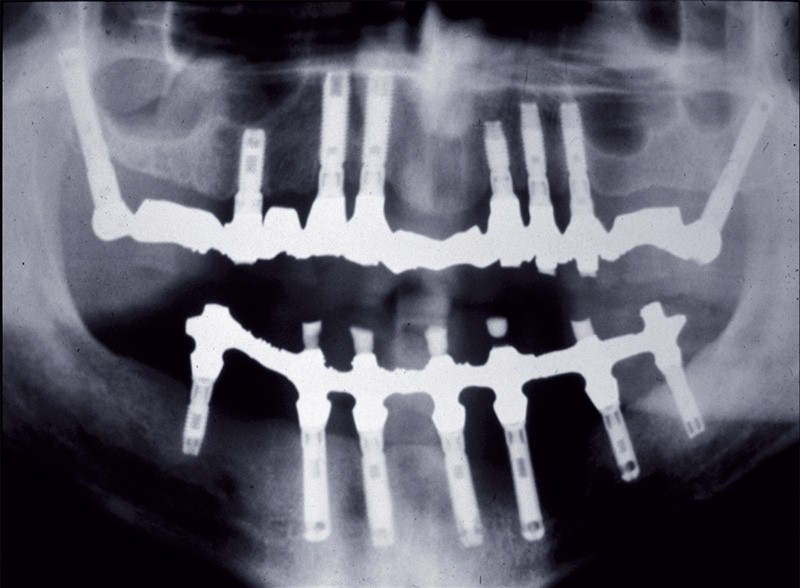

Trois mois plus tard, le patient s’inquiète de l’apparition d’une vaste masse tumorale dans la même zone (fig. 1).

Un cliché panoramique a été effectué (fig. 2). Il permettait de constater une vaste aire d’ostéolyse entourant l’implant et allant jusqu’à son apex. Ce patient était particulièrement ordonné : il avait conservé un cliché postopératoire révélant, autour du même implant, une structure osseuse absolument normale (fig. 3).